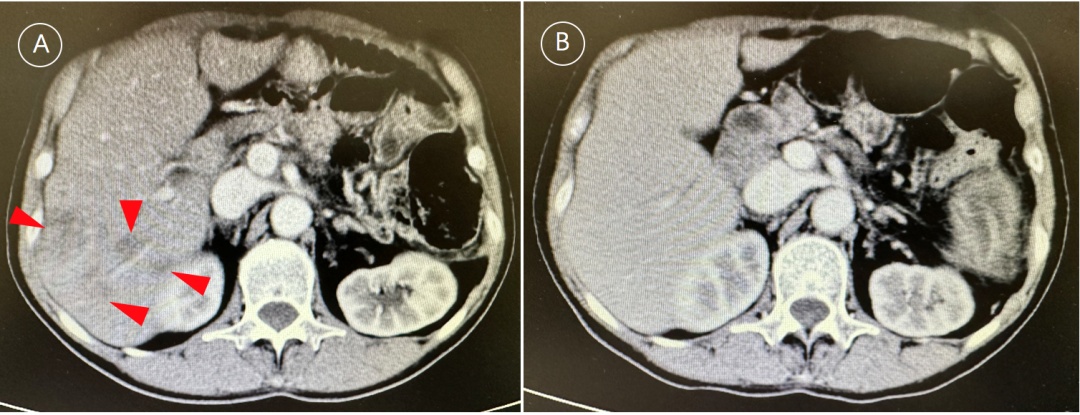

龚伟主任领衔的肝胆胰MDT团队在这时再一次发挥了重要作用,经过讨论,专家们为秦阿姨更改化疗方案的同时加入了免疫治疗。2个疗程后,肝转移灶就明显缩小,6个疗程后,肝转移灶完全消失,为了巩固治疗效果,专家们建议她继续做了7个疗程的治疗。

化疗后出现肝转移灶(A)及化疗+免疫治疗后转移灶完全消失(B)